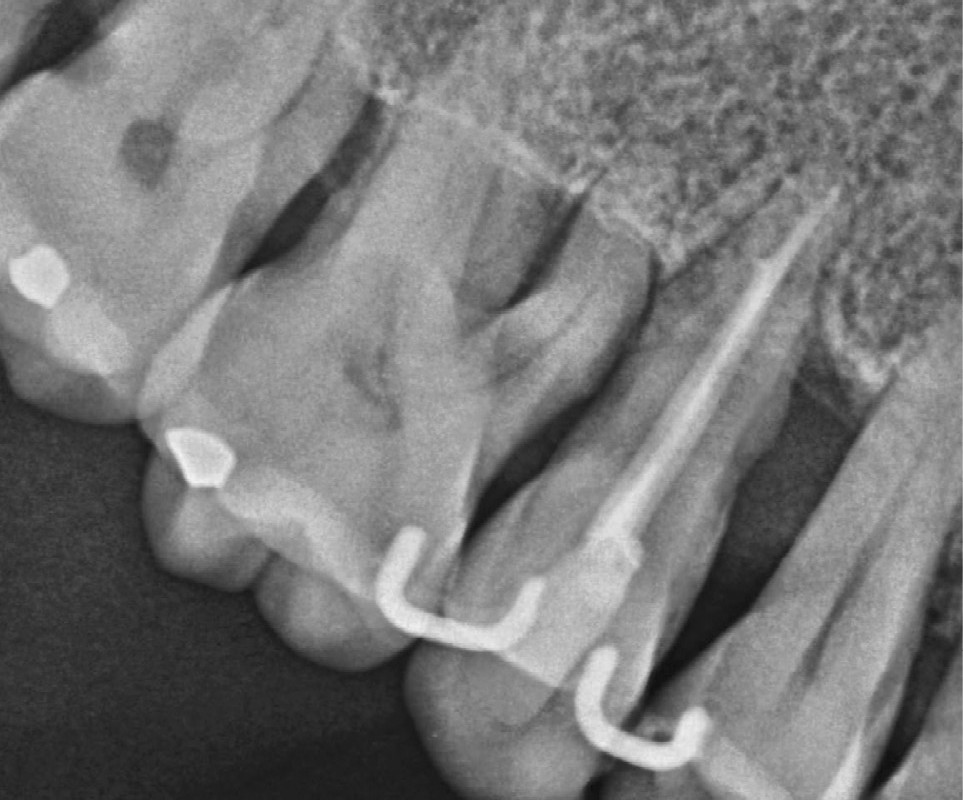

b. 7 ans après, la dent est toujours présente. Notez l’image radiologique de « corticalisation » et la réduction de l’espace ligamentaire qui suggère une stabilisation.